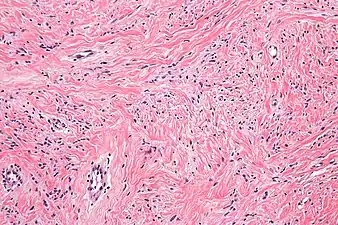

High mag. Mammary myofibroblastoma

Medical imaging may suggest but cannot prove that a tumor is MFB. Mammography, computed tomography scans, and magnetic resonance imaging of mammary[1][12] and extramammary[1][13] MFB typically show well-defined and well-circumscribed tumors which in almost all cases have no calcifications; these results suggest that the tumor is not malignant but do not indicate which type it might be. The diagnosis of MFB depends on the microscopic histopathology (i.e. appearances after proper tissue preparation and staining) of its pre-surgery biopsied issues. As shown in the upper image and the two images in the Additional images section seen below, both mammary and extramammary MFB tissues contain spindle cells, variable numbers of adipocytes (i.e. fat cells) and broad sheets or, less often, thick bundles of collagen fibers.[5] About 4% of cases have an epithelial tumor cell-like morphology,[5] i.e. the tissues are composed predominantly of epithelioid cells variably mixed with a minority (10% to 40%) of round, polygonal, and spindle-shaped cells.[19] Unlike malignant tumors, MFB tumors do not have: a) atypical cells except in the rare cases which contain small clumps of multinucleated cells; b) rapidly proliferating cells as defined by measuring the proliferative index (i.e. fraction of cells undergoing mitosis); or c) areas of necrosis (i.e. areas of dead or dying cells).[16] Microscopy of tumors in the spindle cell lipoma tentative variant of MFB show a mixture of mature fat cells, ropey collagen, and spindle cells in a myxoid (i.e. background connective tissue that stains blue or purple rather than the red of normal connective tissue) matrix.[18] The blood vessels in these tumors often appear hyalinized.[16] Tumor tissues in the tentative cellular angiofibroma variant of MFB contain spindle cells in all cases, fat cells in ~50& of cases, mast cells, peri-vascular infiltrates of lymphocytes, pleomorphic cells in some cases, and cells with some features of the malignant sarcoma cells in sarcoma tumors in rare cases. (The presence of these sarcoma-like cells does not seem to impact the prognosis of this variant.) All of these cells are in edematous-to-fibrous stromatous tissue.[16]